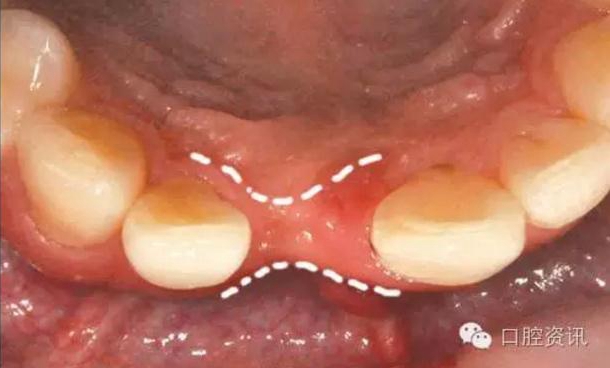

正如前面介紹過,一些重要結(jié)構(gòu)(如下頜神經(jīng)、上頜竇) 的位置和形態(tài)

會影響種植體植入的位置。有些患者的牙槽骨萎縮較嚴重,也會導致

沒有足夠的牙槽骨來承托種植體,增加了手術(shù)難度。有時候,雖然有

足夠量的牙槽骨,骨質(zhì)卻很稀疏,也會影響種植體和骨結(jié)合的效率。

通常拍攝X光片可以幫助來確認牙槽骨的質(zhì)量和剩余量,如果骨量不

夠,您還需要在植牙手術(shù)前或同時,接受骨增量手術(shù)。

11.jpg

圖11. 拔牙后出現(xiàn)牙床萎縮